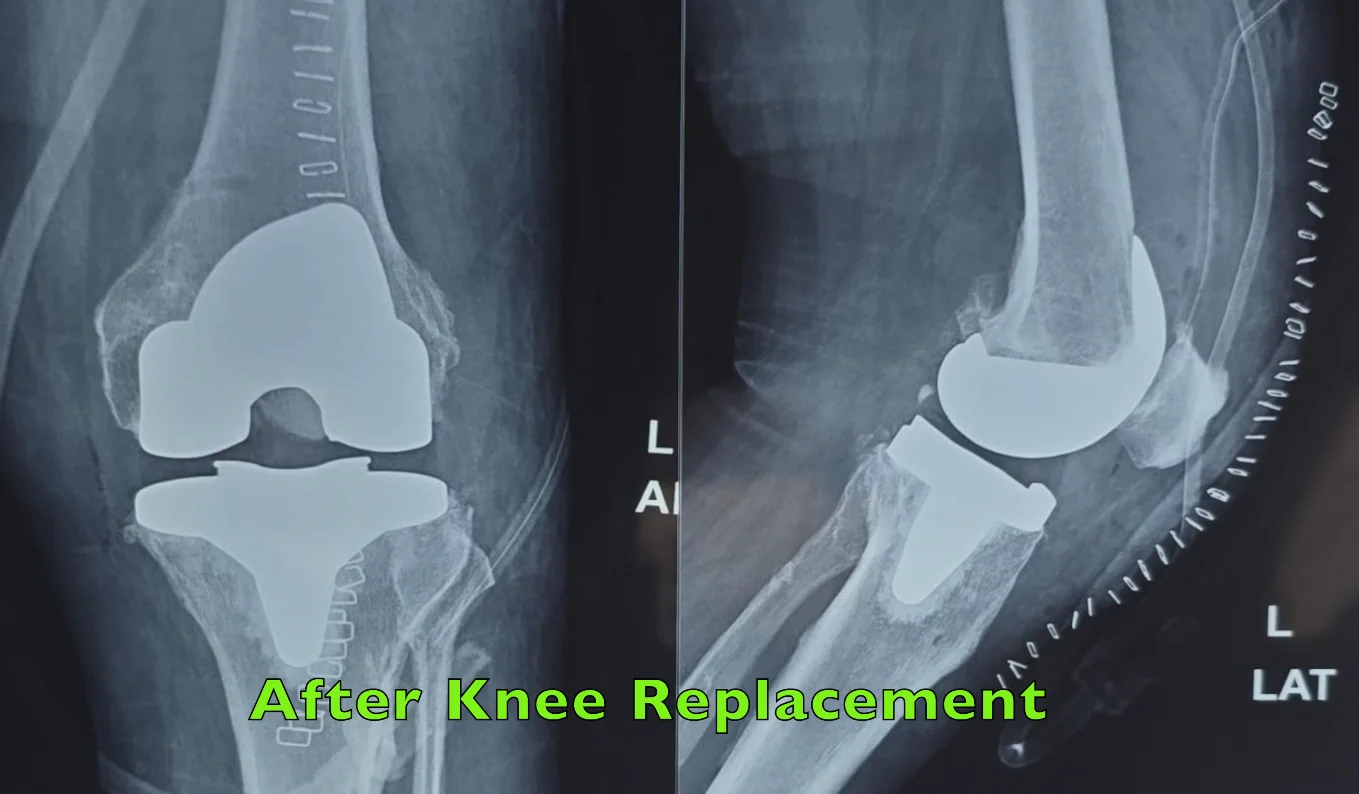

Knee replacement surgery (knee arthroplasty) involves replacing the damaged surfaces of your knee joint with an artificial implant.

How the Surgery Is Performed

During knee replacement surgery:

Robotic assistance may be used to ensure accurate alignment and a well-balanced knee.